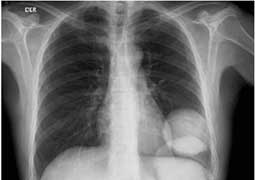

X-ray image showing internal body structures

Both CT and conventional x-rays take pictures of internal body structures. In conventional x-rays, the structures overlap. For example, the ribs overlay the lung and heart. In an x-ray, structures of medical concern are often obscured by other organs or bones, making diagnosis difficult.